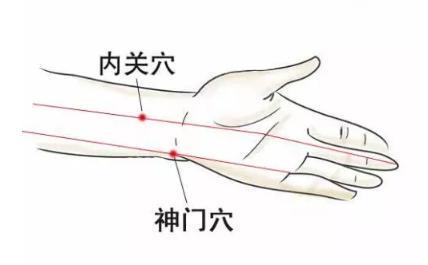

補心氣安神可以用拇指按揉以下穴位:內關、神門、三陰交。

內關穴位於掌心面,手腕橫紋上2寸(每個人自身大拇指的寬度為1寸) ,掌長肌腱與橈側腕屈肌腱之間。

神門穴位於手腕內側,小指延伸至手腕關節與手掌相連一側的腕橫紋中,屈肌腱的凹陷處。